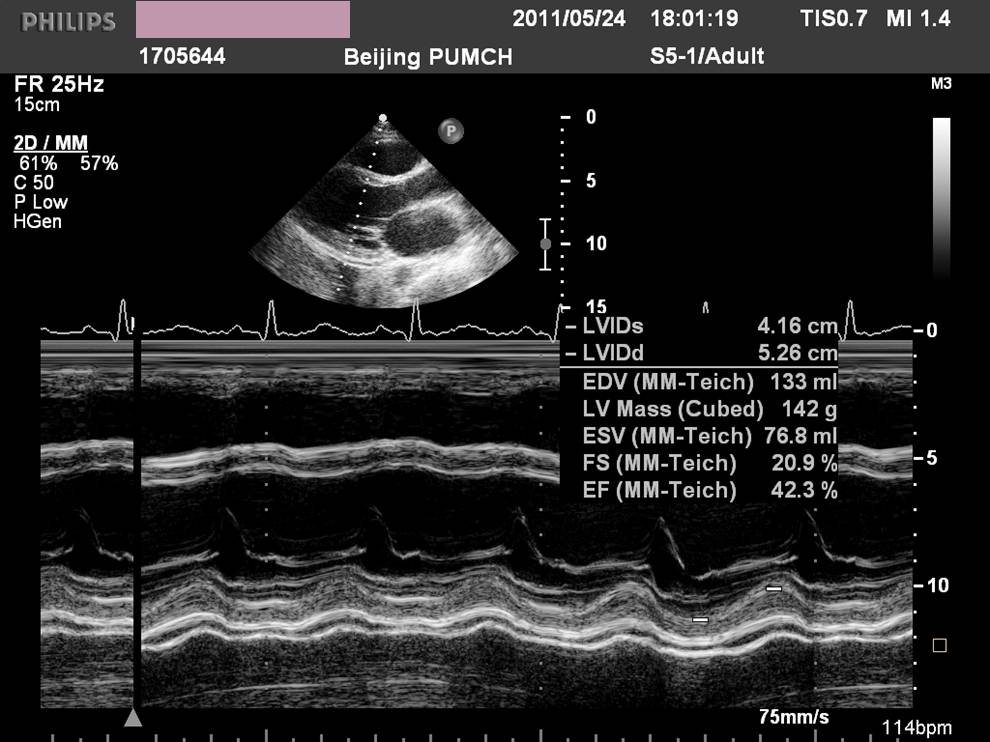

——床旁超声心动:节段性室壁运动异常,左房增大,轻度二尖瓣关闭不全,左室收缩功能减低,LVEF 45%,少量心包积液

现病史-超声心动

急性左心收缩功能不全

心功能不全IV级